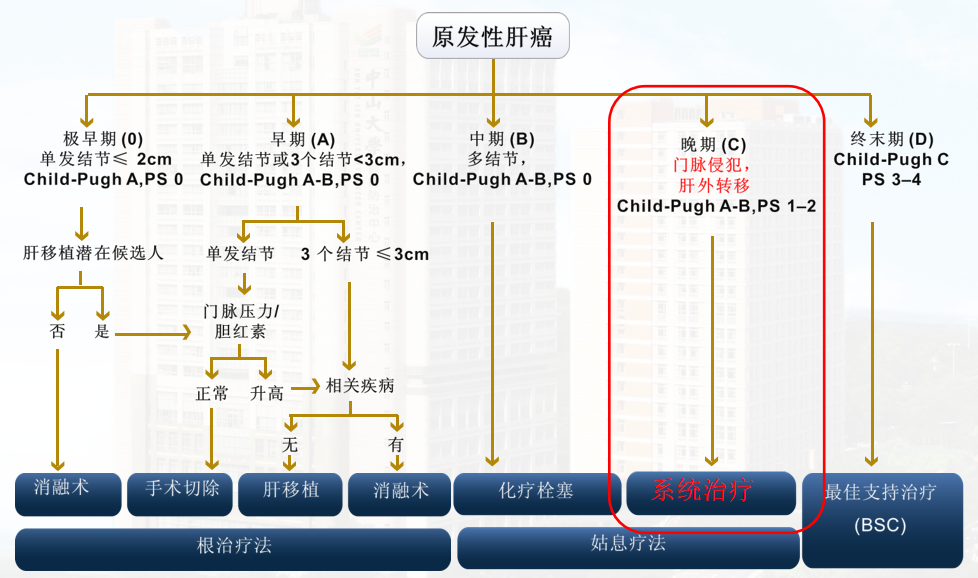

按2018版BCLC分期的治疗方案: